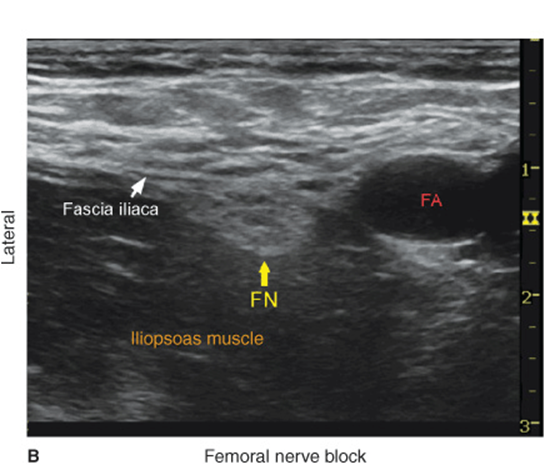

Orientation begins with the identification of the pulsating femoral artery at the level of the inguinal crease. If it is not immediately recognized, sliding the transducer medially and laterally will bring the vessel into view eventually. Immediately lateral to the vessel, and deep to the fascia iliaca is the femoral nerve, which is typically hyperechoic and roughly triangular or oval in shape (Figure 35-2A and B). The nerve is positioned in a sulcus in the iliopsoas muscle underneath the fascia iliaca. Other structures that can be visualized are the femoral vein (medial to the artery) and occasionally the fascia lata (superficial in the subcutaneous layer). The femoral nerve typically is visualized at a depth of 2- to 4-cm.

FIGURE 35-2. (A) Cross-sectional anatomy of the femoral nerve (FN) at the level of the femoral crease. FN is seen on the surface of the iliopsoas muscle covered by fascia iliaca. (white arrows). Femoral artery (FA) and femoral vein (FV) are seen enveloped in their own vascular fascial sheath created by one of the layers of fascia lata. (B) Sonoanatomy of the FN at the femoral triangle.